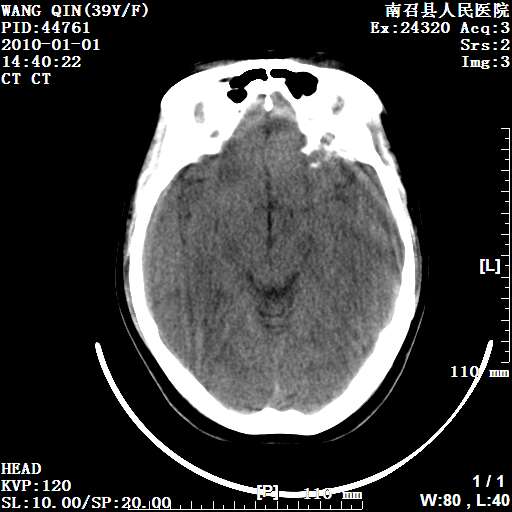

以下是引用随光逐影在2010-1-22 9:03:00的发言:[br]考虑左侧中颅窝(蝶骨翼区)脑膜瘤侵犯蝶骨翼并突入左侧眼眶。

以下是引用水过无痕在2010-1-22 14:55:00的发言:[br]一、定位:颅外占位;二、定性:恶性可能性大;三、组织来源:来源于左侧眼外直肌或其他部位;考虑为:横纹肌肉瘤>转移瘤>脑膜瘤.